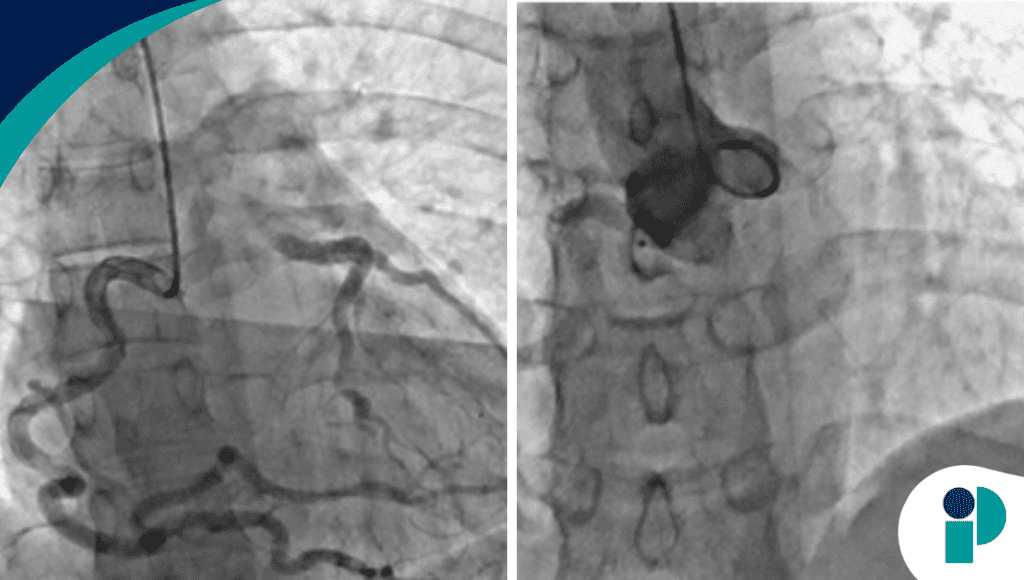

El diagnóstico se confirmó mediante angiografía, evidenciando el origen anómalo de la arteria coronaria izquierda desde la arteria pulmonar (ALCAPA), con circulación colateral extensa que había permitido la supervivencia hasta la adultez.

A pesar de la función ventricular preservada, la paciente presentaba isquemia miocárdica inducida por el esfuerzo, explicada por el fenómeno de robo coronario, en el que la sangre fluye de forma retrógrada hacia la arteria pulmonar en lugar de perfundir el miocardio.